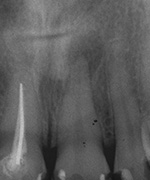

3 Aufnahmen sind von 2001, die vierte vom Nov. 2006

Aufbissempfindlichkeit an 33 veranlasste uns erstmalig in dieser Kieferregion zu röntgen. Mit grossen Augen sahen wir dann an, was uns auch ansah. Einen Knochendefekt dieser Grössenordnung mit seiner schaurigen Aura sieht man zum Glück nicht jeden Tag. Doch, obgleich das Alien dereinst Zahn 34 entsprang, war eine Behandlung nur am Zahn davor durchsetzbar. Dessen Wurzelfüllung erfolgte regulär nach 14 Tagen, neue Terminangebote aber wurden, weil angeblich nicht mehr nötig, verschmäht.

Keine 8 Wochen gingen noch in's Land, bis das mit Macht geschah, was lange schon erwartet war. Das Arbeitsprogramm bestand aus Eröffnung von Zahn 34 und einer Schwellung inkl. Drainage, am nächsten Tag dann noch Aufbereitung des Kanals mit Einlage. 2 Wochen später dann die Füllung plus einem als Resektion deklarierten Auslöffeln des Granu­lationsgewebes durch eine Mini-Öffnung, zu deren Verschluss eine Naht genügte.